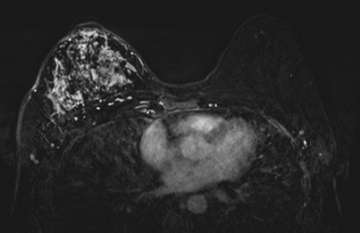

Case: Inflammatory Breast Cancer Figure 2

Figure 2. An axial contrast-enhanced fat-saturated T1-weighted MR imaging demonstrates abnormal diffuse non-mass enhancement occupying the almost entire right breast.